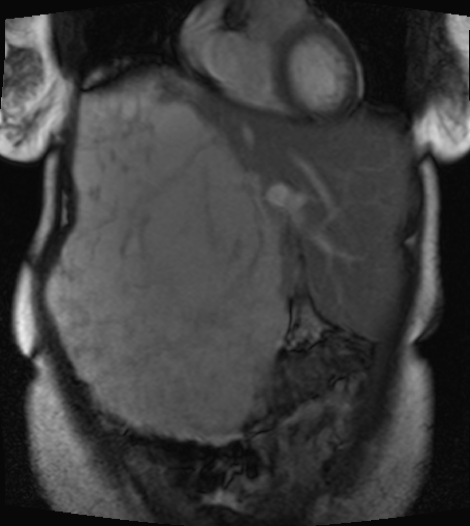

A magnetic resonance imaging (MRI) scan of the abdomen 2 years ago without IV contrast had revealed a large multilocular and septate mixed-intensity liver lesion involving essentially all of the right lobe, measuring 26 × 18 × 16 cm (Figure 3). MRI with IV contrast indicated a progressive peripheral pattern of nodular enhancement, which was strongly suggestive of a giant hepatic hemangioma. No splenomegaly was present.

Figure 3. T2-weighted MRI scan showing a lesion involving essentially all of the right lobe of the liver.

MRI is typically used to diagnose giant hepatic hemangiomas. Giant hemangiomas can show heterogeneity centrally if thrombosis or fibrosis is present and hyperintensity on T2-weighted MRI with globular enhancement peripherally.